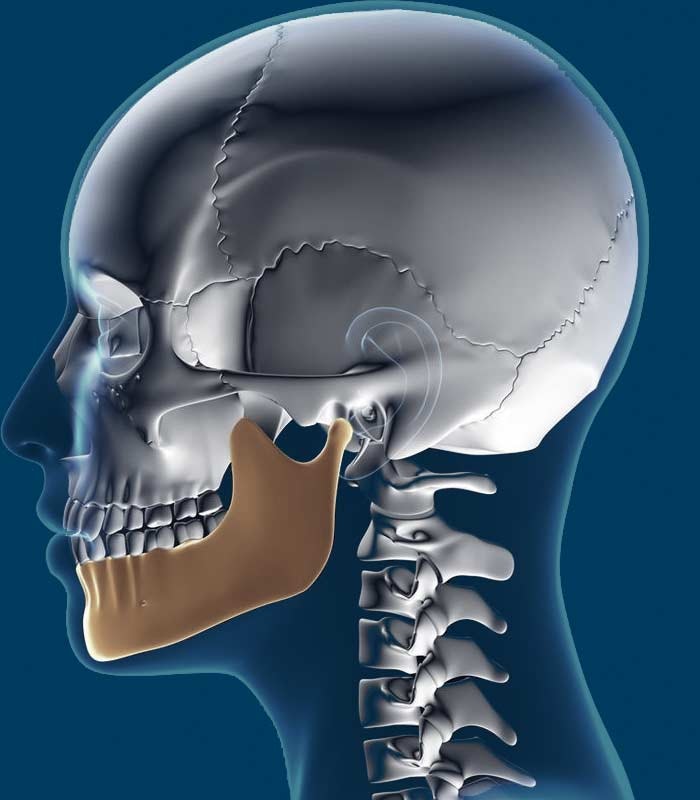

- Corrective jaw surgery

Jaw Surgery

The ultimate goal for a maxillofacial surgeon is to repair any damage done and restore function to your smile. What those results will look like depends on the patient's needs and the treatments in question. While frenectomy or extraction will have immediate results, placing dental implants or completing corrective jaw surgery requires months of recovery before your body adjusts.